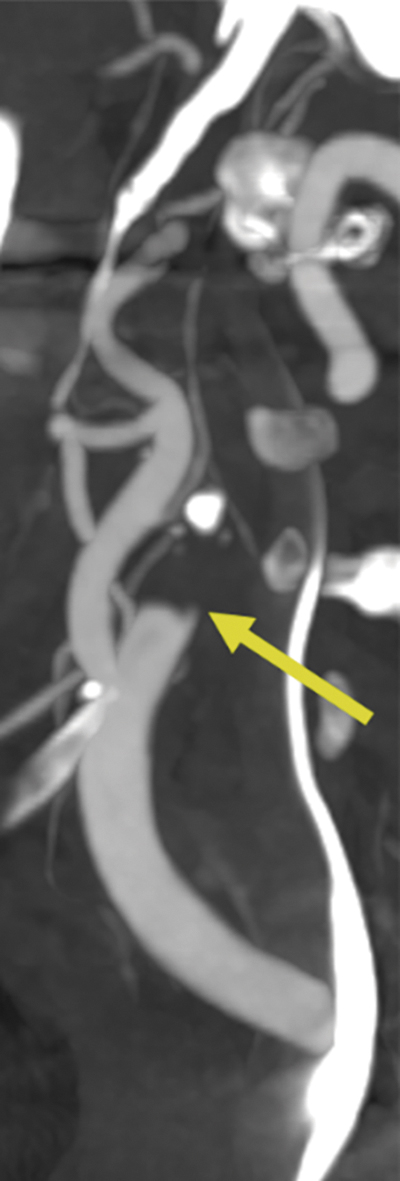

2. Presença de padrão de falha de enchimento  com morfologia em “chama de vela” (chamado  de beak pattern) na ACI: logo após a bifurcação,  observa-se um afilamento gradual antes de haver  a parada da contrastação4. A especificidade desse  critério aumenta para 100% diante da identificação  conjunta de uma redução gradual na intensidade  da contrastação desse segmento do vaso, ou seja,  quanto mais cranial, menos intenso é o contraste5 (figura 1B e 1C).

Na figura 1, a morfologia do segmento proximal da ACI cervical, logo após o bulbo, foi avaliada.  O padrão “chama de vela” teve alta acurácia para reconhecer a pseudo-oclusão.Figura 1. Neste caso de AVCI agudo, observa-se, no  plano coronal, oclusão do T carotídeo (seta em A).  No plano sagital (B), não há contrastação de toda  a artéria carótida interna (ACI) direita cervical e a  interrupção do fluxo é antecedida por afilamento  gradual (“chama de vela”) e redução gradual da  atenuação do contraste (seta em B). As imagens  C e D mostram cortes axiais no mesmo nível, sendo  o C na fase arterial e o D na fase venosa. As setas  mostram que a ACI direita não apresentava  contrastação na fase arterial e passou a apresentar  enchimento na fase venosa (tardia).